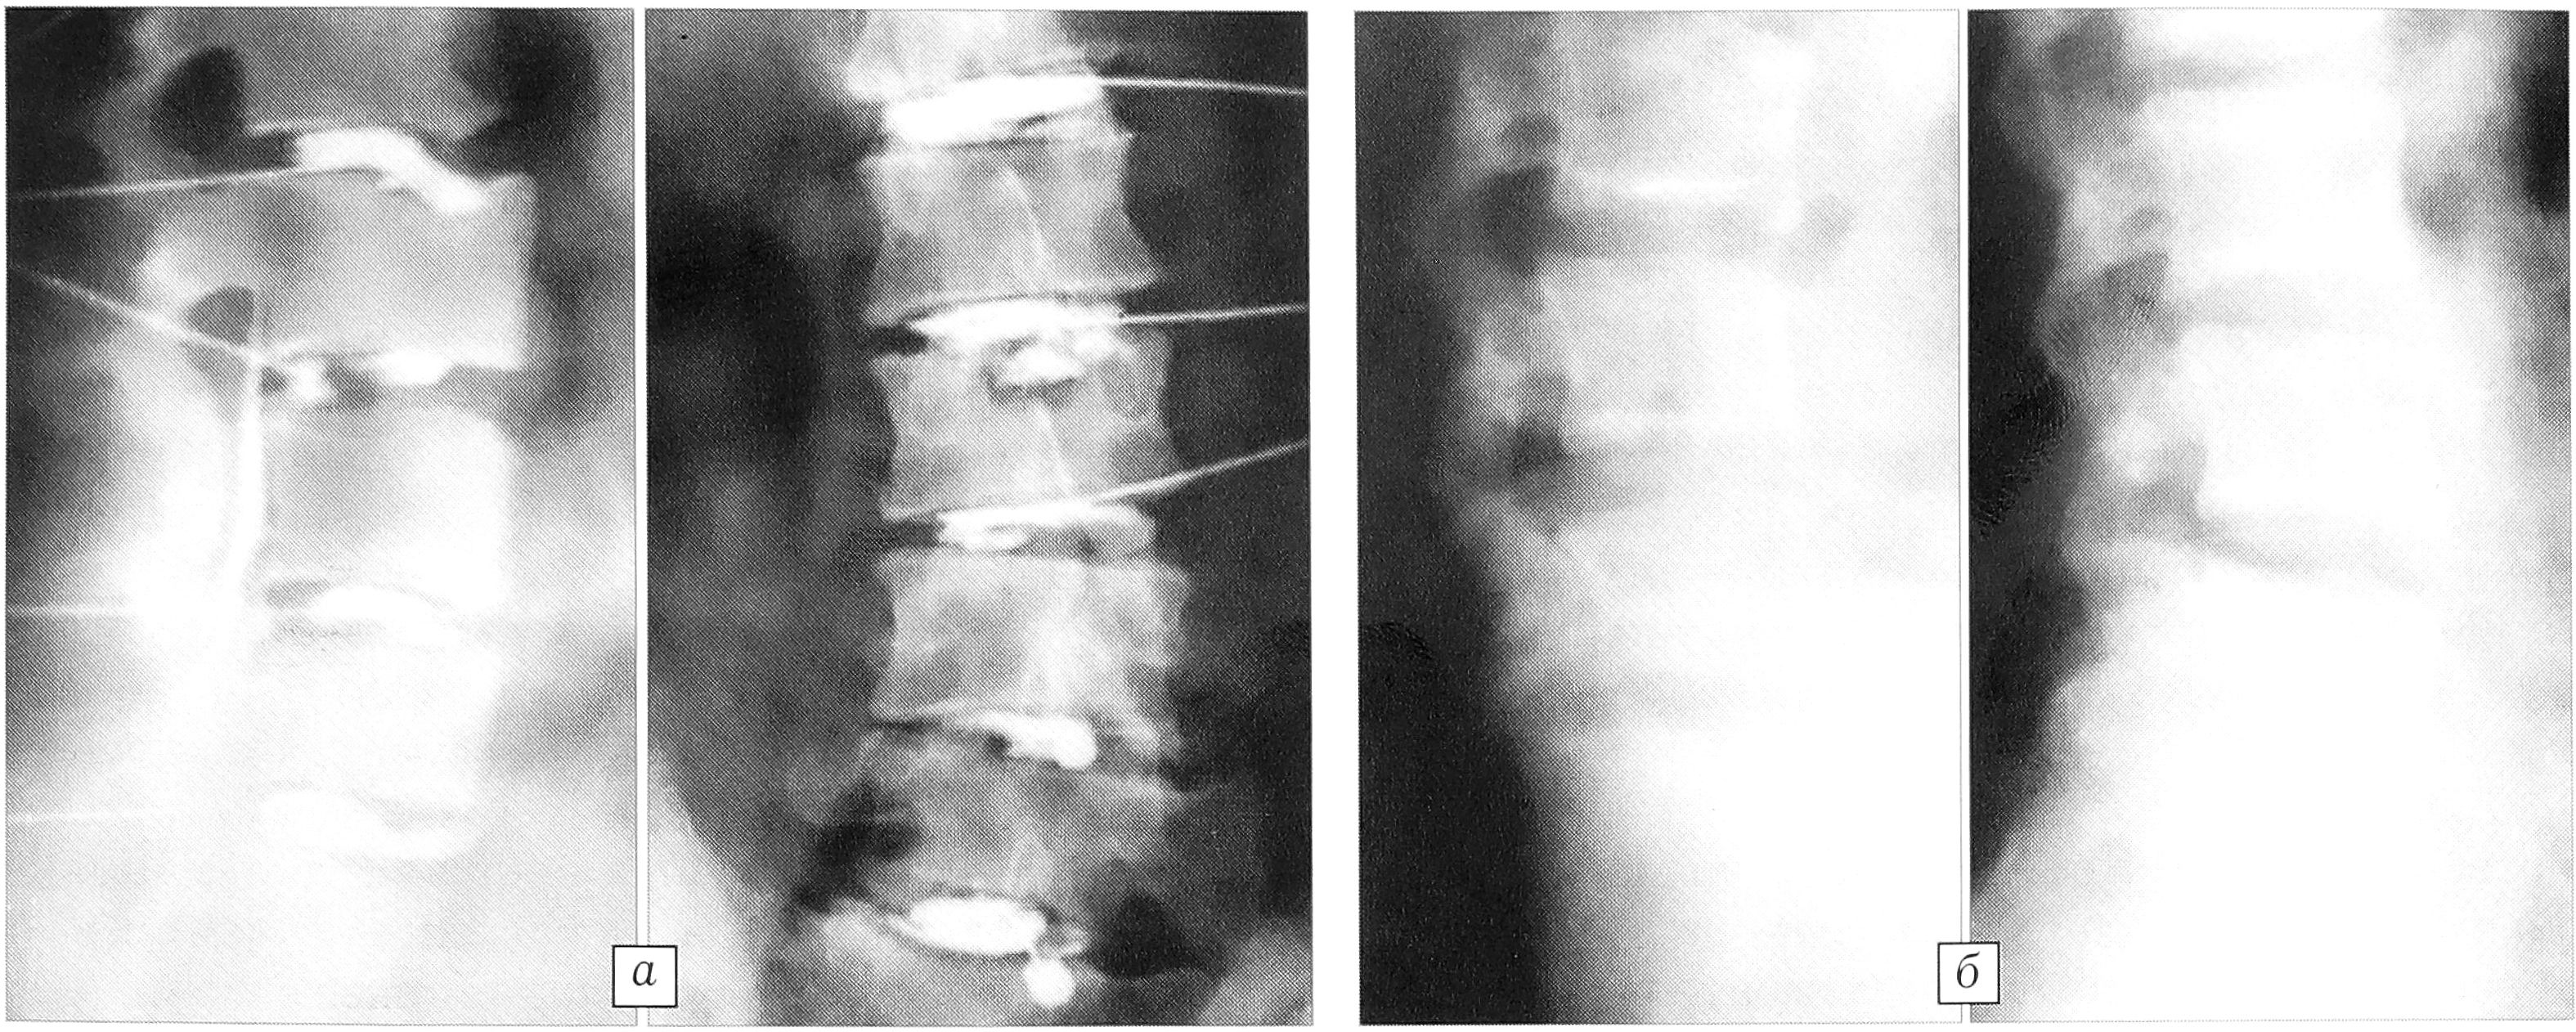

В системе пораженного сегмента наступает декомпенсация опорной, двигательной и защитной функций. Это проявляется различными сочетаниями основных клинических синдромов: дискалгии, спондилоартралгии, нестабильности позвоночных сегментов, а также стеноза позвоночного канала (рис. 8).

Рис. 8. Развернутая клиническая картина остеохондропатии: грыжа L4-5 диска, нестабильность L3-4, L4-5 сегментов, увеличение стеноза позвоночного канала на уровне L3-4, L4-5 сегментов при разгибании (а — сгибание, б — разгибание).